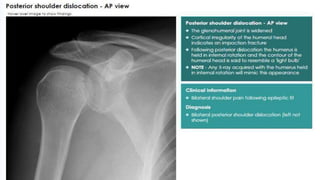

• In the AP film the humeral head, because it is medially

rotated, looks abnormal in shape (like an electric light bulb)

and it stands away somewhat from the glenoid fossa (the

‘empty glenoid’ sign).

• An Axillary view is essential; it shows posterior subluxation

or dislocation and sometimes a deep indentation on the

anterior aspect of the humeral head.